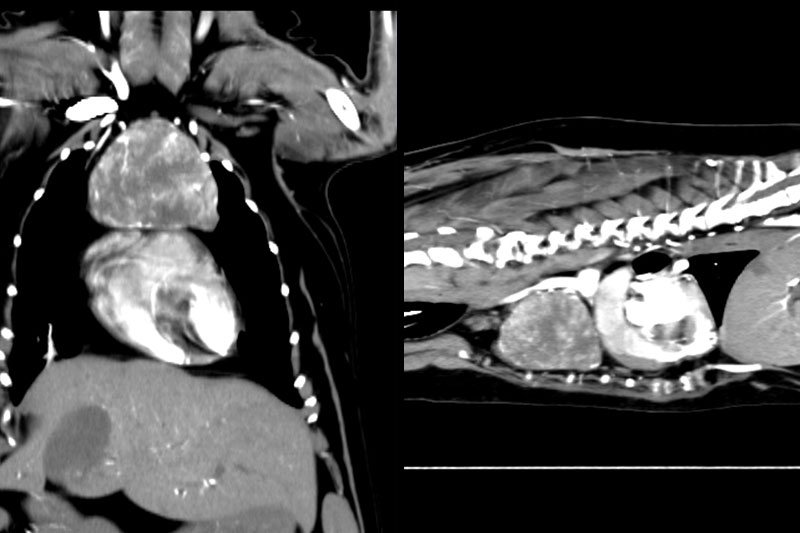

CT (Computed Tomography, 전산화 단층촬영) 검사는 X-ray를 이용해 반려동물의 몸을 여러 각도에서 촬영하고, 이를 컴퓨터로 합성하여 단면 이미지(슬라이스)를 만들어내는 정밀 진단 장비입니다.

사람 병원에서도 널리 사용하는 기술로, 뼈, 장기, 혈관, 종양 등 몸속 구조를 3차원(3D)으로 시각화할 수 있습니다.

| 복부 | 간, 비장, 신장, 위장관 종양 및 결석, 부신, 림프절 등 |

복부 장기의 종양, 염증, 결석, 기형 등 고해상도 분석